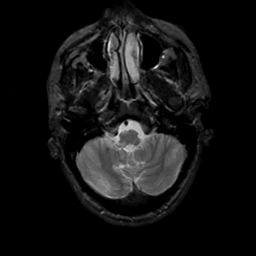

MR Study #12, May 12, 1991 -- Slice #8

[Home][Help][Clinical][Tour 1][Tour 2] Slice 8